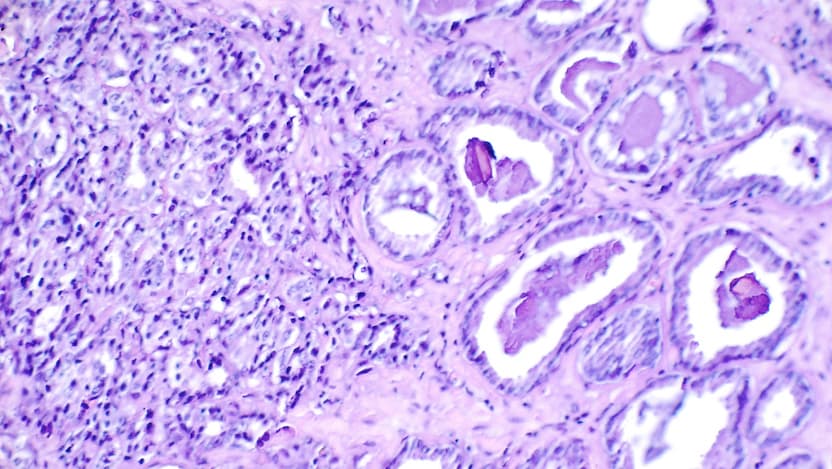

Prostate cancer is the most common cancer and the second leading cause of cancer death among men in the United States. Metastatic, castrate-resistant prostate cancer (mCRPC) is an incurable form of prostate cancer that keeps growing even when the amount of testosterone in the body is reduced to very low levels. Researchers are looking for new treatment options to use for mCRPC.

Rucaparib (trademarked as Rubraca®) is one of a new class of anticancer drugs called poly (ADP-ribose) polymerase inhibitors, or PARP inhibitors, which work by targeting cancer cells that have a defect in how they repair damage to their DNA. PARP inhibitors are already successfully used to treat ovarian cancers and some inherited forms of breast and pancreatic cancer.